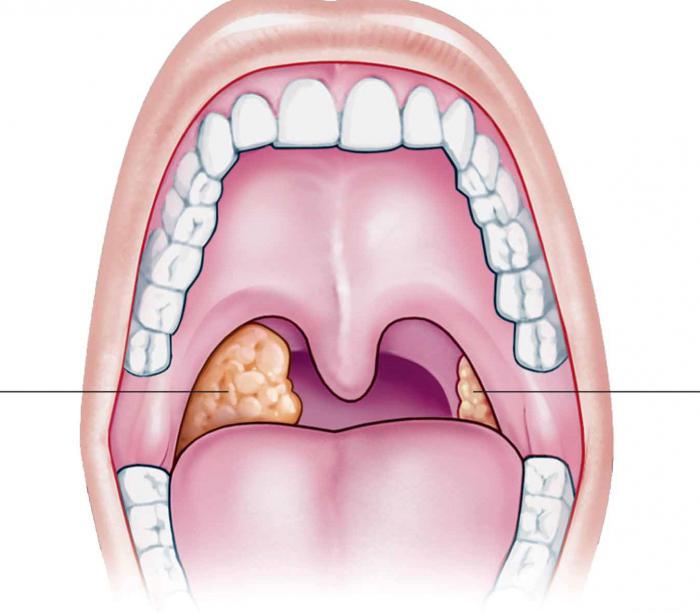

• Amigdalitis